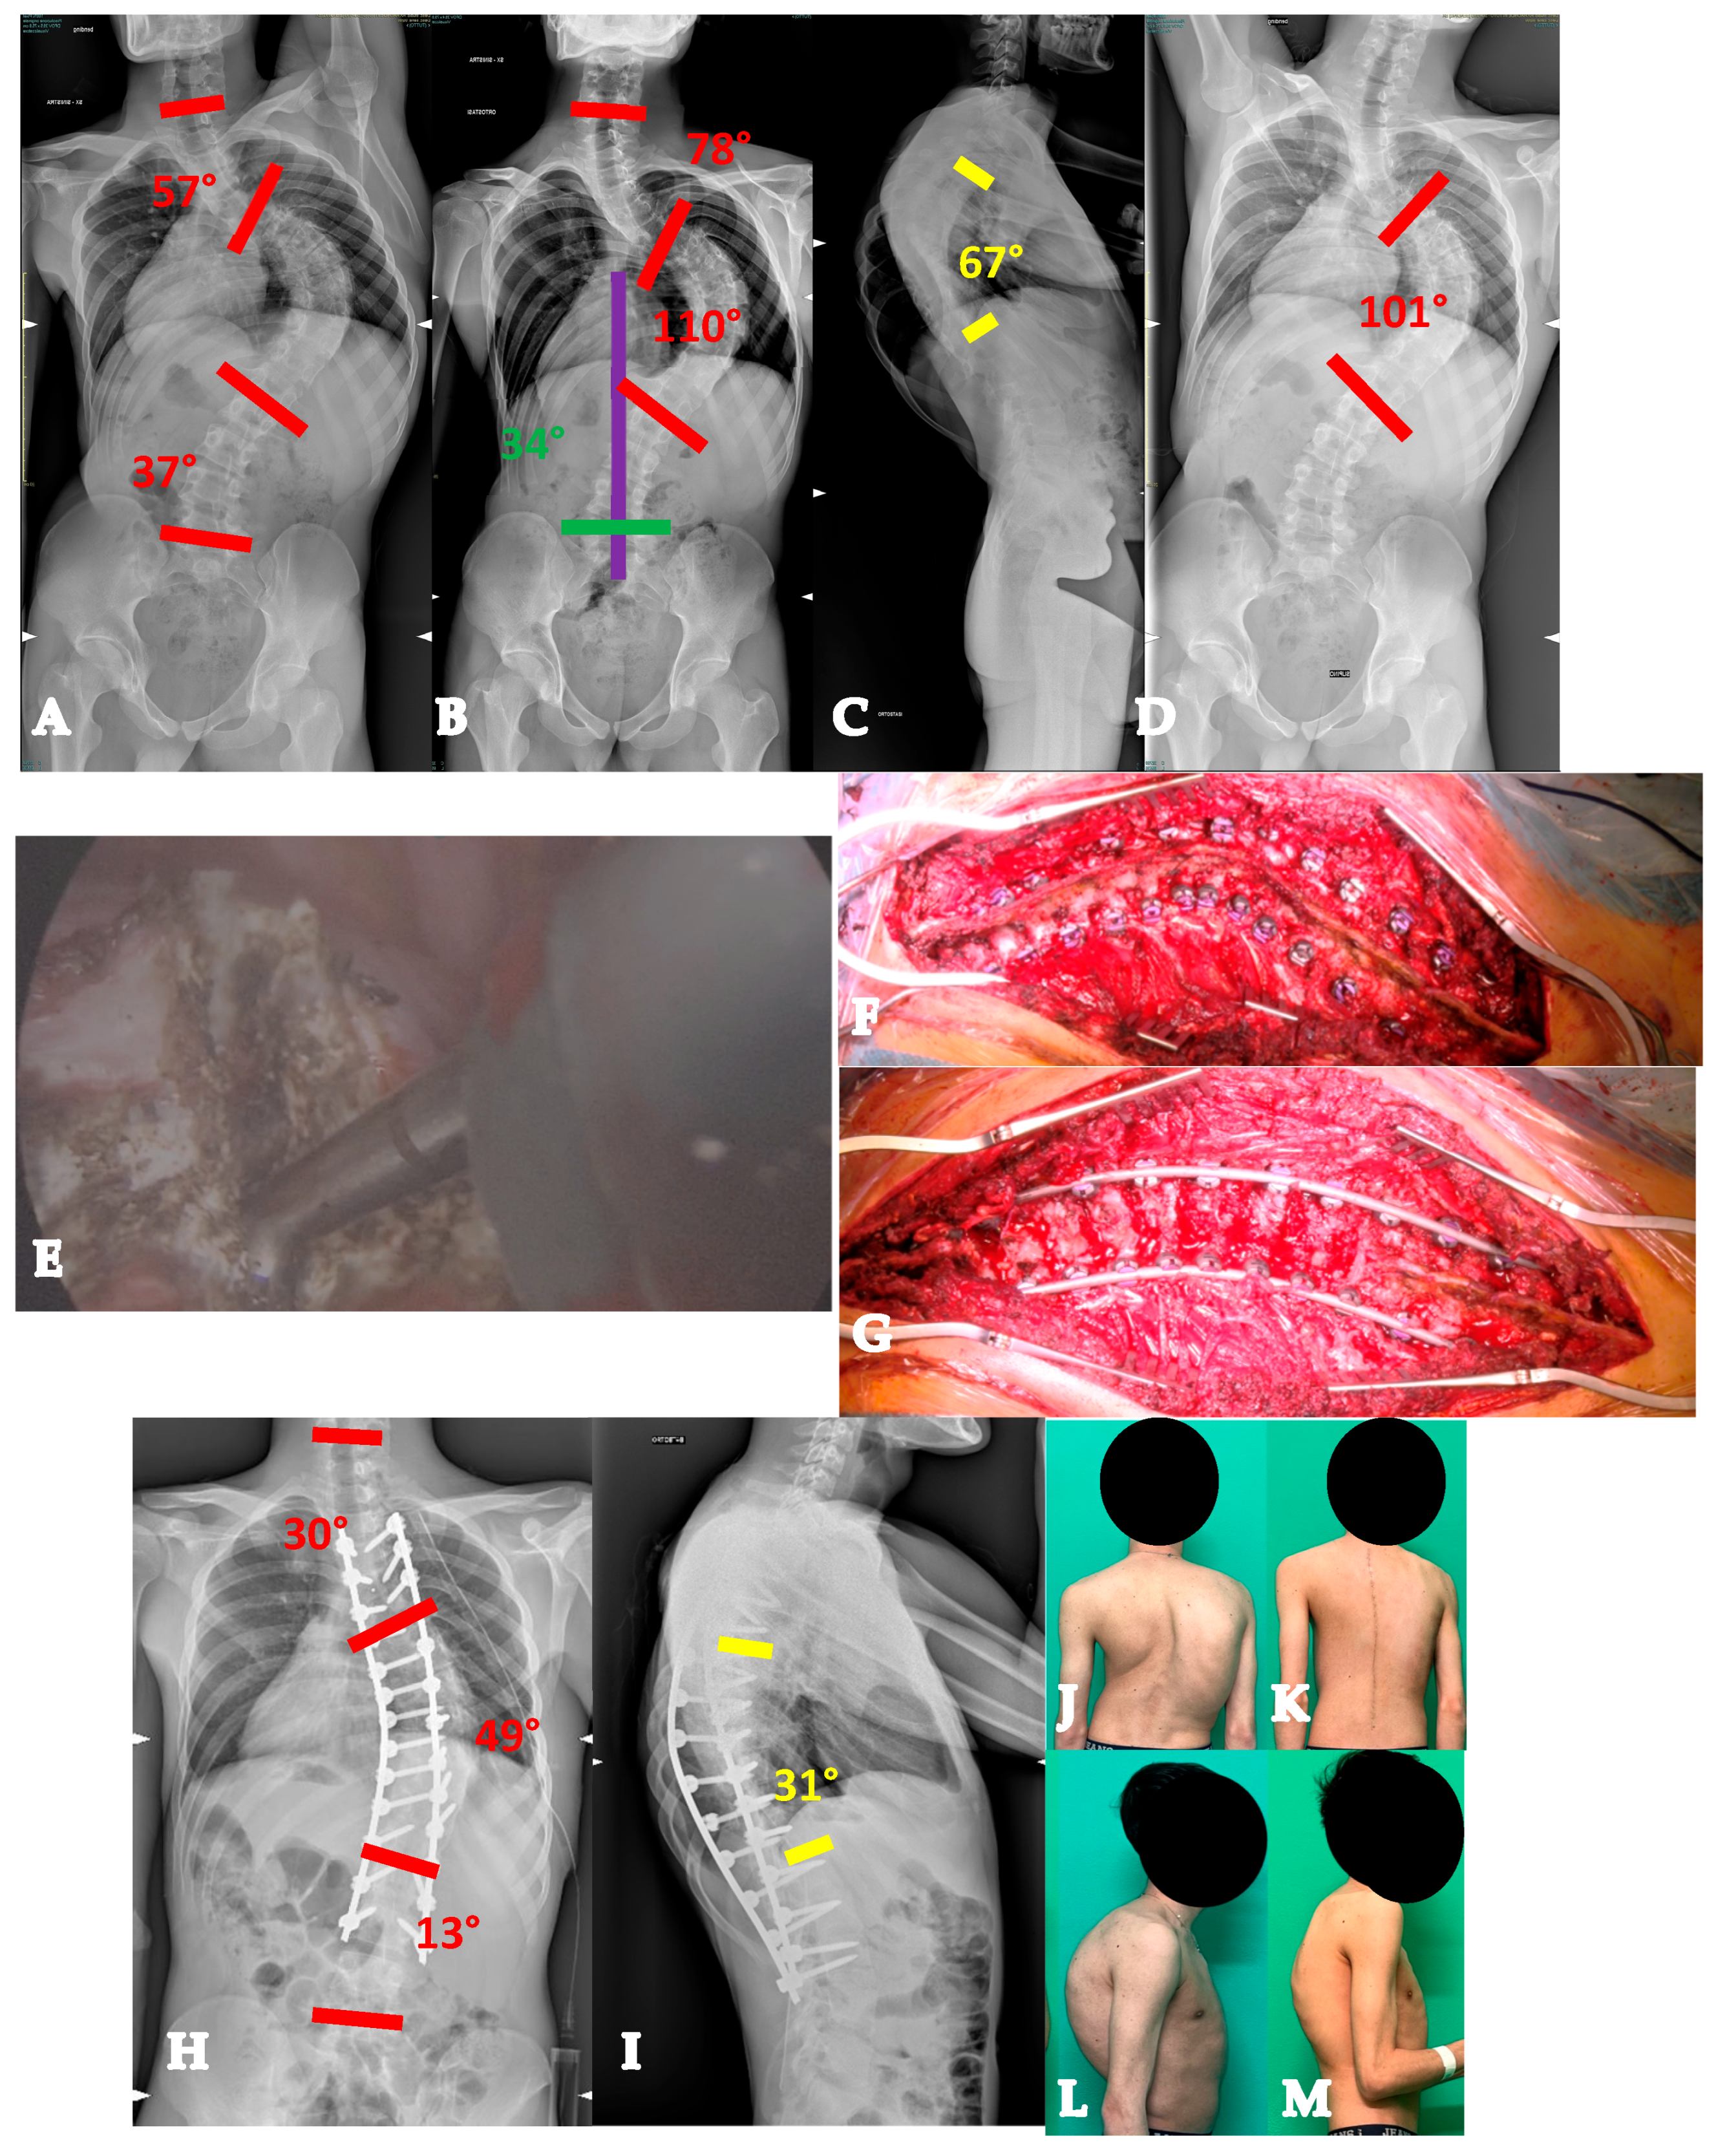

- For curves ≥ 90° AND with a flexibility index < 15% (YADIS 2B), the HiPoAD technique, even though it proved to be effective for this kind of curve when addressed during adolescent years [12], may not be powerful enough for YAdIS 2 patients. These cases should be addressed with a three-columnar approach. One strategy could be to adopt three-column osteotomies like VCR. A possible alternative, in order to avoid the risks of a three-column osteotomy, is to perform a three-columnar release through a combined approach: an anterior thoracoscopic release (wide resection of anterior longitudinal ligament and multiple periapical discectomies), followed by a posterior column release based on multiple Ponte Osteotomies and a posterior correction (VT-HiPoAD, Videothoracoscopic release—HiPoAD) (Figure 4).